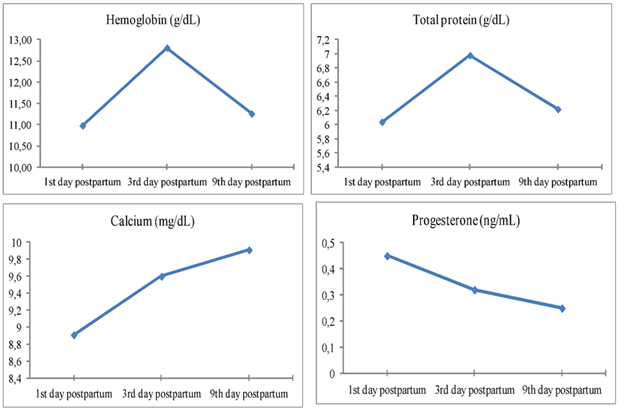

The concentrations of hemoglobin, total protein, calcium and progesterone were measured at the 1st, 3rd and 9th days postpartum and the mean of the 3 measures were calculated. The mean values of the hemoglobin, total protein, calcium and progesterone in the 3 measures were within the reference ranges, although there were significant changes between the repeated measures (Table 3 and Table 4). Hemoglobin concentration significantly increased in the 3rd day (12.81 ± 0.426 g/dL) (p=0.012) compared to the 1st day postpartum (10.98 ± 0.176 g/dL) (Figure 1a). Total protein showed significant increase in the 3rd day (6.98 ± 0.201 g/dL) (p=0.003) compared to the 1st day postpartum (6.04 ± 0.112 g/dL) (Figure 1b). Calcium concentration showed significant increase in the 9th day (9.91 ± 0.209 mg/dL) (p=0.002) compared to the 1st (8.91 ± 0.084 mg/dL) and the 3rd days postpartum (9.6 ± 0.257 mg/dL) (Figure 1c). Progesterone concentration showed significant sharp decrease after parturition compared to the reference values of progesterone in normal conditions, in addition, there were marked significant decrease in the 9th day (0.25 ± 0.024 ng/mL) (p=0.004) compared to the 1st (0.45 ± 0.066 ng/mL) and the 3rd days postpartum (0.32 ± 0.039 ng/mL) (Figure 1d).

Figure 1.Illustrate the changes in the hemoglobin (a), total protein (b), calcium (c) and progesterone (d) during the 1st, 3rd and 9th days postpartum in female camels.